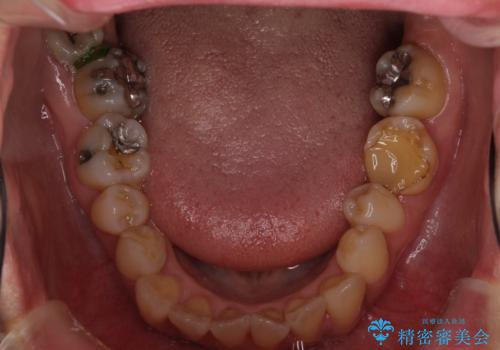

- 前歯の反対咬合により、日々強い痛みを感じているとのことで来院された患者様です。

骨格的に下顎が前方位にありますが、歯列矯正で前歯の被蓋関係を改善することができると判断されたため、インビザラインにより矯正治療を行うこととしました。

また、上顎前歯と下顎大臼歯に神経を取り除いた歯があったため、矯正治療後に、セラミッククラウンにて補綴することとしました。

前歯が内側に倒れ込む力がかかり、正常な歯ぎしりもできないため、非常に負担のかかりやすい咬み合わせでした。